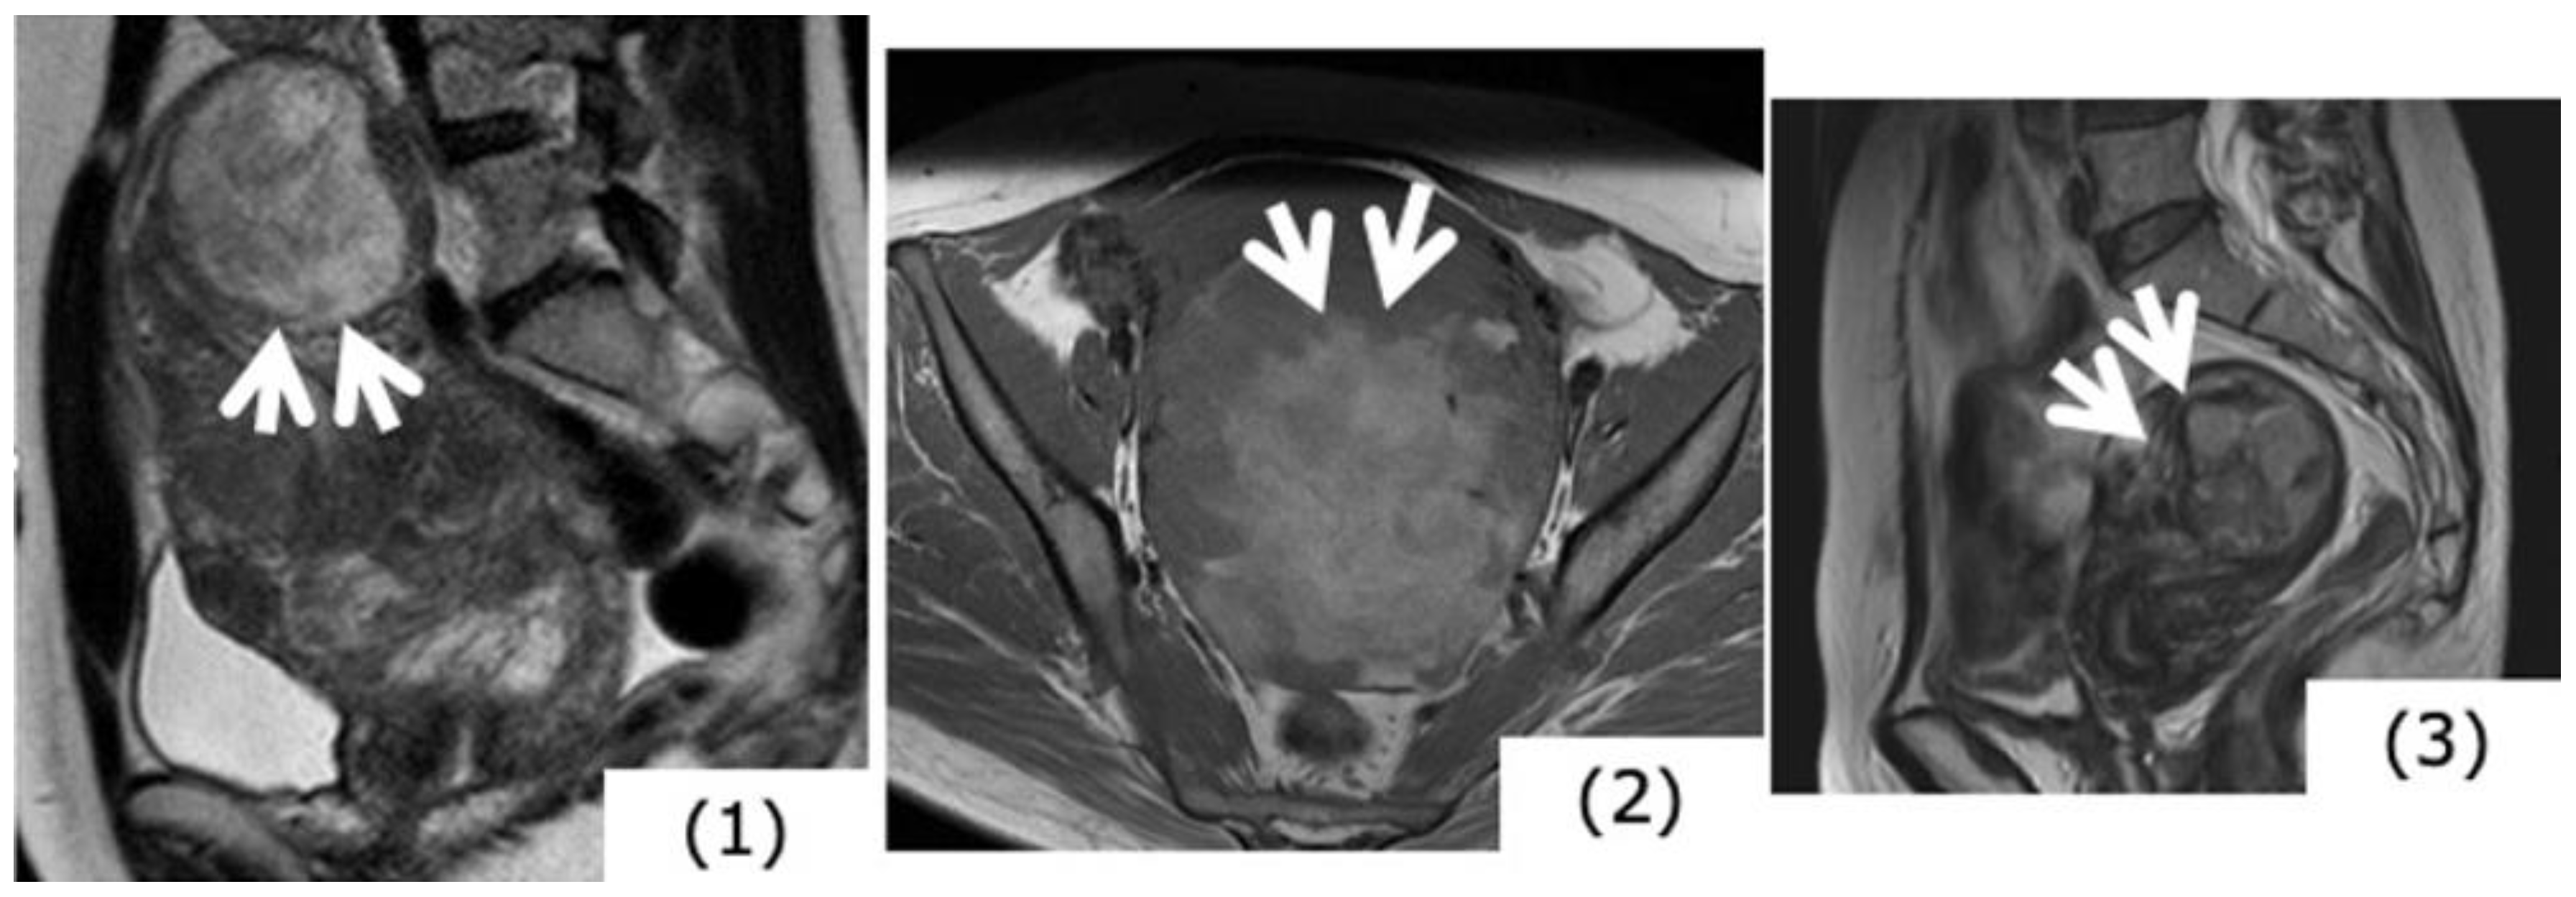

6.2. Leiomyosarcoma

6.3. Endometrial Stromal Sarcoma (ESS)

7. Differentiating between Uterine Myoma and Sarcoma